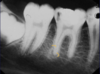

what do we see here

buccal, lingual and why?

- mesiodens- its a tiny tooth, doesnt necesarilly have the shape of a tooth though.

- superimposed at CI and then shift shot see it superimposed with LI, so it has moved to the right

- it is lingual/palatal to the erupting teeth because of SLOB